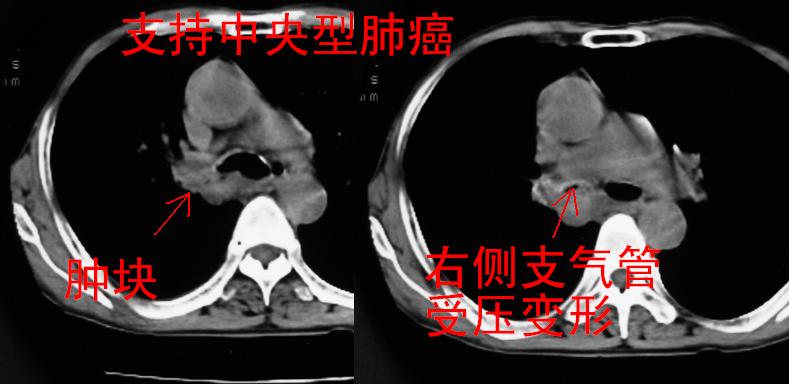

以下是引用同在2007-1-27 14:13:00的发言:[br]支持右侧中央型肺癌伴阻塞性病变.

以下是引用zjzjr在2007-1-27 16:56:00的发言:[br]支持右肺中心型肺癌伴阻塞性肺炎.